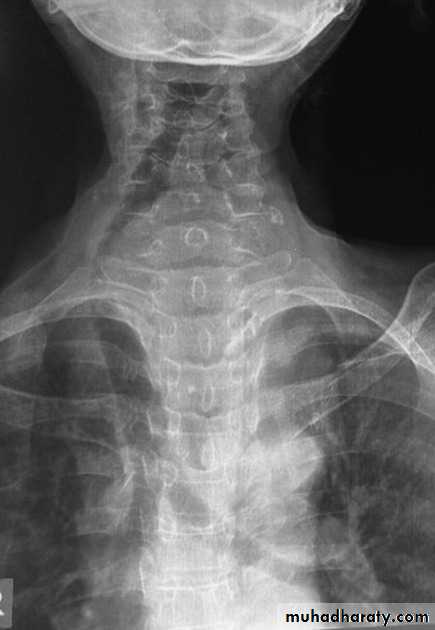

Various Chest disease & their XR findings & appearance

Normal chest XR PA & lateral view

9.normal radiologic anatomy of the chest

10.normal chest anatomy